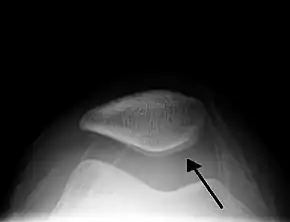

![]() Skyline view of the patella demonstrating a large joint effusion as marked by the arrow | |

| Purpose | Detecting a knee effusion |